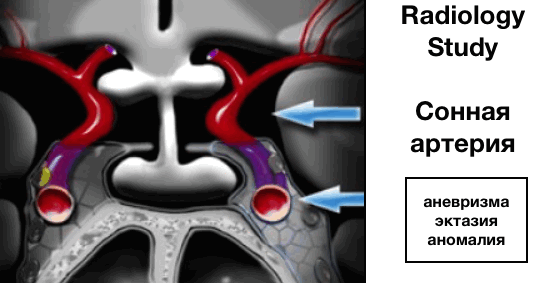

Внутренняя сонная артерия (ВСА)

Далее оцениваются внутренние сонные артерии, которые имеют сложный анатомический ход, проходя сперва через основание черепа, визуализируясь в виде буквы S на боковых срезах, а далее через кавернозные синусы.

Краниальные сегменты ВСА также называют супракавернозными сегменты.

ВСА бифуркируется на ветви:

- передней мозговой артерии (ПМА), проходящие вдоль перекреста зрительных нервов

- средней мозговой артерии (СМА), проходящие латеральнее.

Наиболее частые патологии:

- аневризма

- эктазия

- аномалия развития сосудов, в том числе медиальное расположение ВСА (практически по медиальной линии).

Ограничения методов

МРТ превосходит КТ по качеству визуализации и оценки размеров кисты Ратке. Сагиттальные и корональные МРТ-снимки позволяют получить достоверную информацию о взаимном расположении образования и зрительных нервов, зрительного перекреста и гипоталамуса. МРТ в корональной проекции также позволяет выявить латеральное распространение кисты за пределы турецкого седла и оценить ее расположение относительно внутренних сонных артерий и кавернозных синусов. Метод Магнитно резонанстной томографии превосходит КТ по возможностям мультипланарной визуализации и контрастного разрешения.